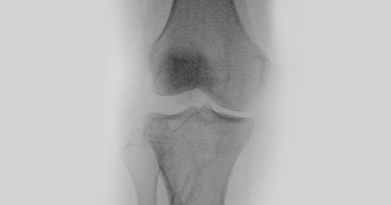

Arthroscopic surgery, is a surgical procedure to visualize, diagnose, and treat problems inside a joint using a specialized instrument known as an arthroscope. An arthroscope is a fiberoptic tube that contains a small lens or camera and a lighting system to magnify and illuminate structures inside a joint.